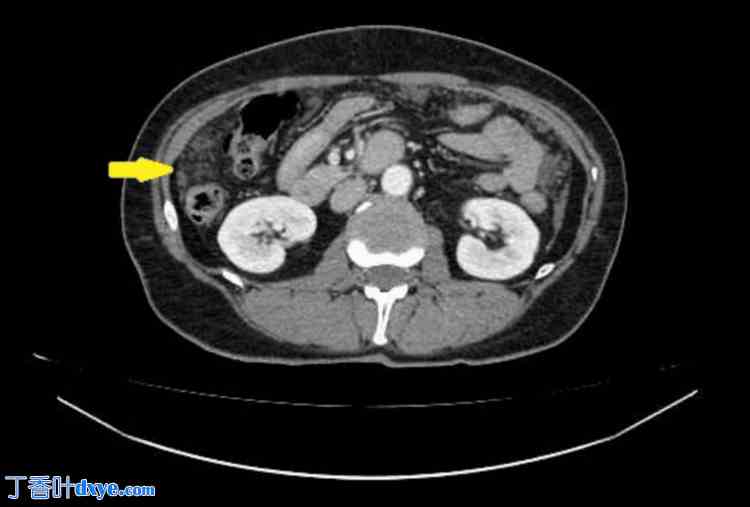

胸部、腹部和盆腔CT扫描(静脉注射造影剂)显示肝周、脾周及盆腔内多处低密度积液(提示为粘蛋白)。在大网膜、小网膜及侧沟内发现聚集性腹膜沉积物,提示腹膜广泛受累。胸部和腹部器官未见其他病理改变。扫描区域淋巴结未肿大。未见骨质破坏或成骨细胞活动征象(图1-4)。

图1. 腹部和盆腔腹膜转移及局部积液的CT影像

箭头(从上至下)分别表示小网膜转移、左侧管转移和脾周积液。